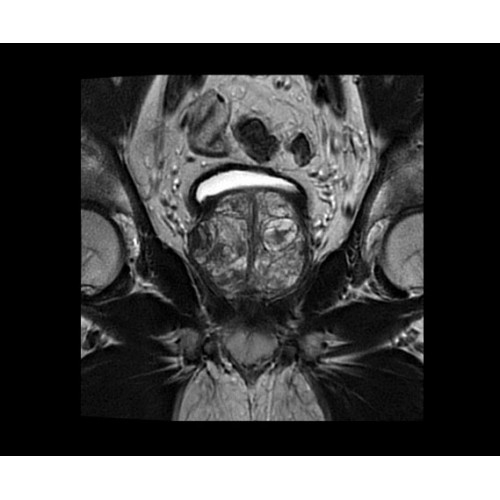

• BodyWorks — для визуализации абдоминальной и тазовой областей, подстраиваясь под запросы пользователя с учетом любых типов пациентов.

• OrthoWorks — программное решение для визуализации структур опорно-двигательного аппарата с прекрасным контрастированием тканей.